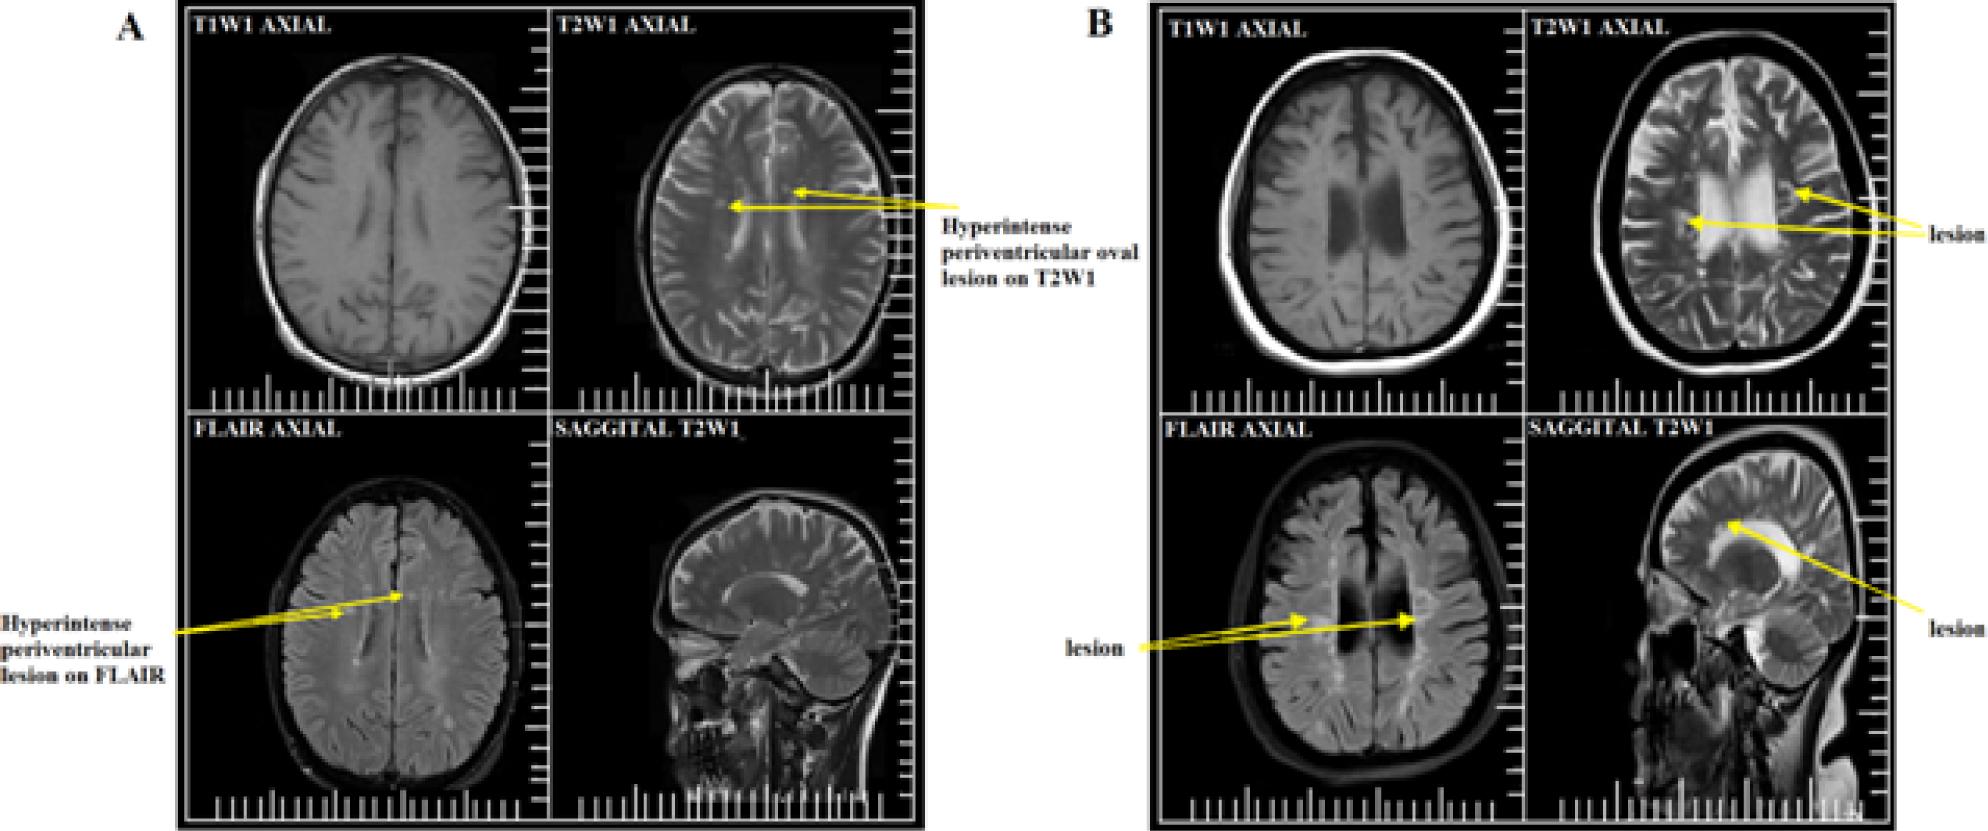

Detection of multiple sclerosis plaques by magnetic resonance imaging

| Sequences | Lesions detected |

|---|---|

| T1W1 | 47 |

| T2W1 | 99 |

| Flair | 100 |

Distribution of multiple sclerosis plaques in brain parenchyma

| No of lesions Mean | Standard deviation | |

|---|---|---|

| Temporal lobe (n = 9) | 0.2 | 0.63 |

| Juxtacortical (n = 62) | 13.1 | 9.20 |

| Periventricular (n = 96) | 0.1 | – |

| Corpus callosum (n = 2) | 13.7 | 9.33 |

| Infratentorial (n = 16) | 0.7 | 2.65 |

| Temporal (n = 8) | 1.5 | 2.28 |

| Paraventricular (n = 97) | 12.5 | 9.91 |

| Parahippocampus (n = 4) | 13.9 | 9.25 |

| Acute (n = 82) | 0.0 | – |